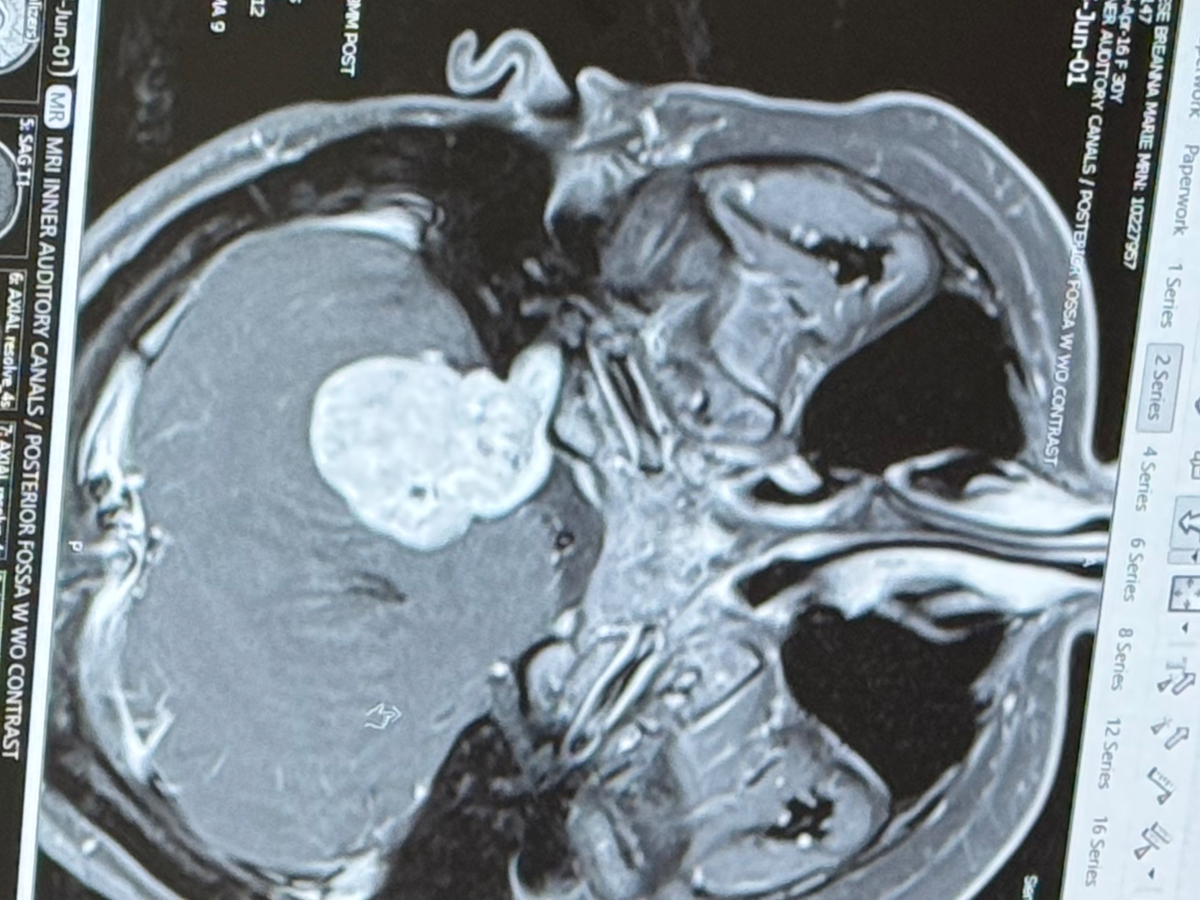

Hello, friends and family. My wife, Bre, and the mother of my kids went into the ER yesterday for ear pressure and found out that she has a big tumor.

It is not cancerous, but she does need surgery, and it's a 12-18 hour surgery with a three-month recovery time. Bre and I will be off work for three months and need help with monthly bills for our house, groceries, etc.